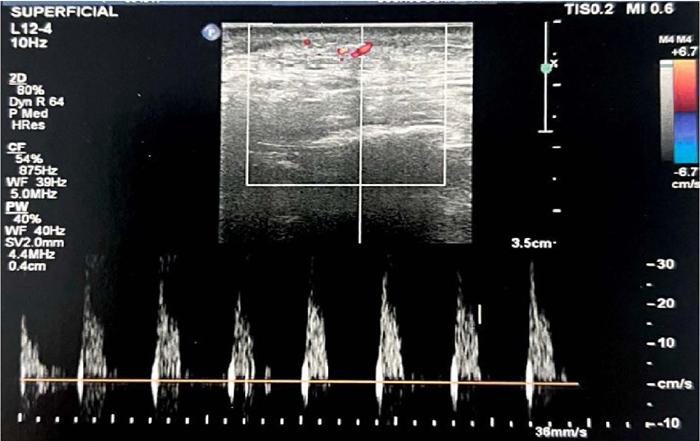

Passadas 72 horas do procedimento, devido à evolução dos sinais de obstrução vascular, como a formação de pústulas e petéquias (Figura 6), realizou-se nova ultrassonografia. Dessa vez, evidenciou-se suboclusão extrínseca da artéria facial transversa, no terço médio (Figura 5). Administrou-se hialuronidase com orientação ultrassonográfica.